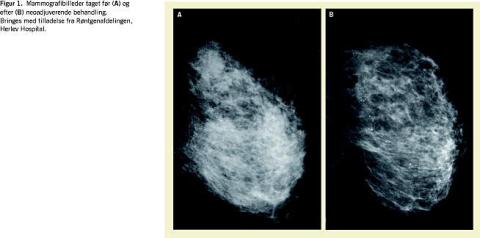

Neoadjuverende eller såkaldt præoperativ systemisk behandling (kemoterapi eller antihormonal behandling) anvendes til behandling af primær inoperabel lokoregional fremskreden brystkræft eller stor operabel brystkræft med primærtumor > 5 cm. Formålet med neoadjuverende behandling ved primær inoperabel brystkræft er at gøre patienten operabel ( down-staging ) og sekundært at udrydde subkliniske fjernmetastaser. Ved primær stor operabel brystkræft er det tillige målet at opnå sufficient tumorreduktion med henblik på at foretage brystbevarende operation i stedet for primær mastektomi. I forhold til standard adjuverende (postoperativ) behandling er der yderligere mulighed for objektiv vurdering af tumorrespons ved brug af neoadjuverende behandling (Figur 1 ), og i tilfælde af manglende effekt er der mulighed for skift til en anden, mere effektiv behandling. Relativ atoksisk antihormonal behandling er oftest en førstevalgsbehandling hos patienter, der har hormonreceptorpositiv sygdom og er ældre eller svækkede med andre konkurrerende medicinske sygdomme og derfor ikke er kandidater til neoadjuverende kemoterapi. Formålet med nærværende oversigtsartikel er at beskrive den nuværende viden om effekten af neoadjuverende antihomonal behandling af primær brystkræft på basis af en litteraturgennemgang.